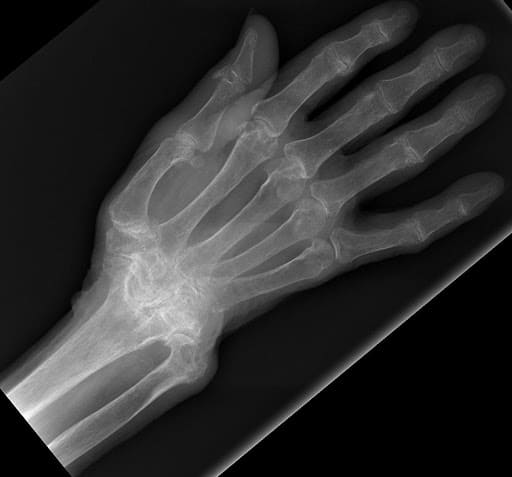

Wrist Scaphoid Fractures